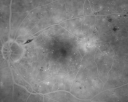

Diabetic Macular Edema Left Eye - Pre Laser524 views82-year-old woman diabetic for many years, last eye exam 5 years ago with gradual vision loss. OD 20/60, OS 20/70. IOP: OD 16, OS 17.

Diabetic Macular Edema Left Eye - Post Laser553 views82-year-old woman diabetic for many years, last eye exam 5 years ago with gradual vision loss. OD 20/60, OS 20/70. IOP: OD 16, OS 17.

Diabetic Macular Edema Left Eye - Post Laser1266 views82-year-old woman diabetic for many years, last eye exam 5 years ago with gradual vision loss. OD 20/60, OS 20/70. IOP: OD 16, OS 17.

OCT SCAN: The OCT scan of the right eye shows retinal atrophy with no intraretinal or subretinal fluid. The left eye has edema temporal to the fovea with involvement of the fovea. Photos confirm clinical findings.

FLUORESCEIN ANGIOGRAM: FA shows multiple microaneurysms in both eyes.

2. CLINICALLY SIGNIFICANT MACULAR EDEMA – LEFT EYE

DISCUSSION: I explained to the patient with focal laser we can reduce the risk of vision loss in the left eye and possibly even improve the vision. I treated the left eye with focal laser today without any difficulty. She will return here for a check in three months, sooner should she notice any problem.